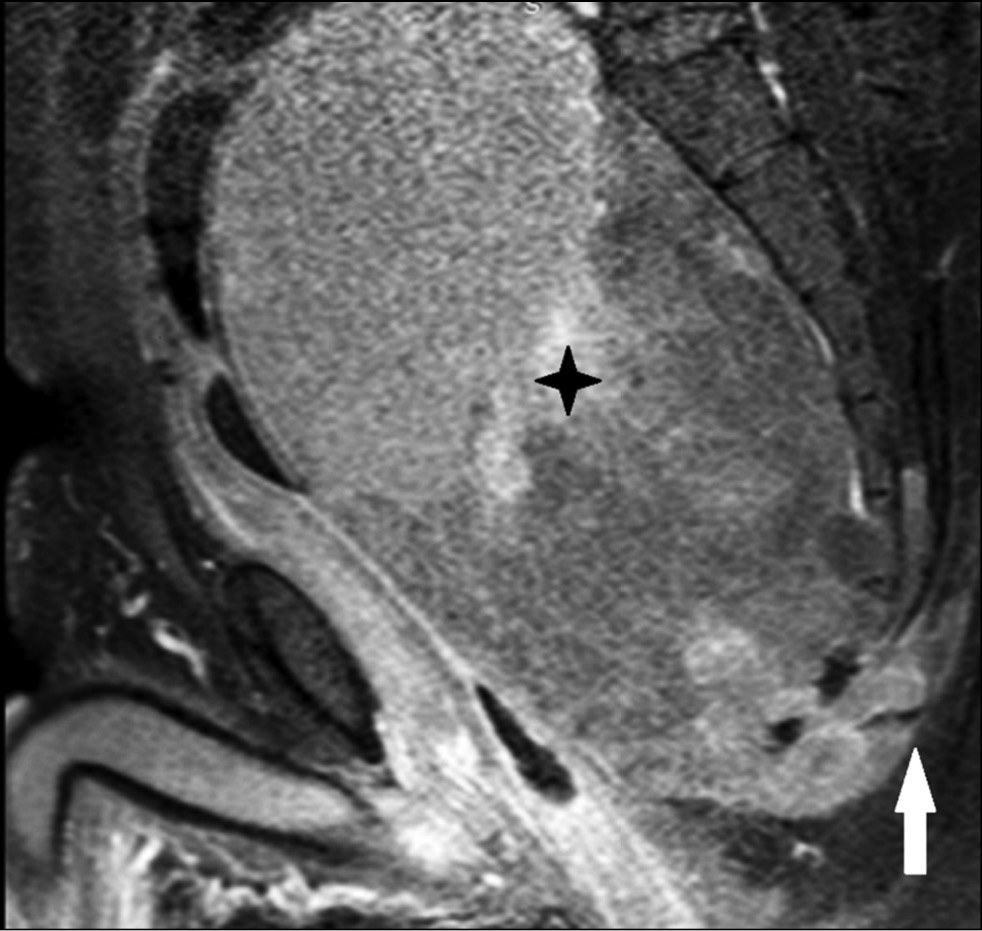

Magnetic resonance imaging (MRI) revealed destruction of the S4, S5, and coccygeal vertebrae with a large soft tissue tumor in the small pelvis and abdomen measuring 200×110×98 mm. The tumor appeared hyperintense in the T2 spectral attenuated inversion recovery mode (Fig. 1) and hypointense in the T1 spectral presaturation with the inversion recovery mode (Fig. 2), causing displacement and deformation of pelvic organs, including the rectum, sigmoid colon, bladder, and ureters.

Fig. 1. T2 SPAIR coronal MRI showing a heterogeneously hyperintense tumor occupying a significant portion of the pelvic cavity (asterisk). Pronounced heterogeneity of the signal is due to areas of hemorrhage.

Fig. 2. MRI in T1 SPIR mode in the sagittal plane: a significant size, heterogeneously hypointense, with moderately hyperintense areas, the intrapelvic soft tissue component of the tumor (asterisk) is adjacent to the anterior surface of the sacrum, infiltrating muscle tissue in the posteroinferior direction (arrow).